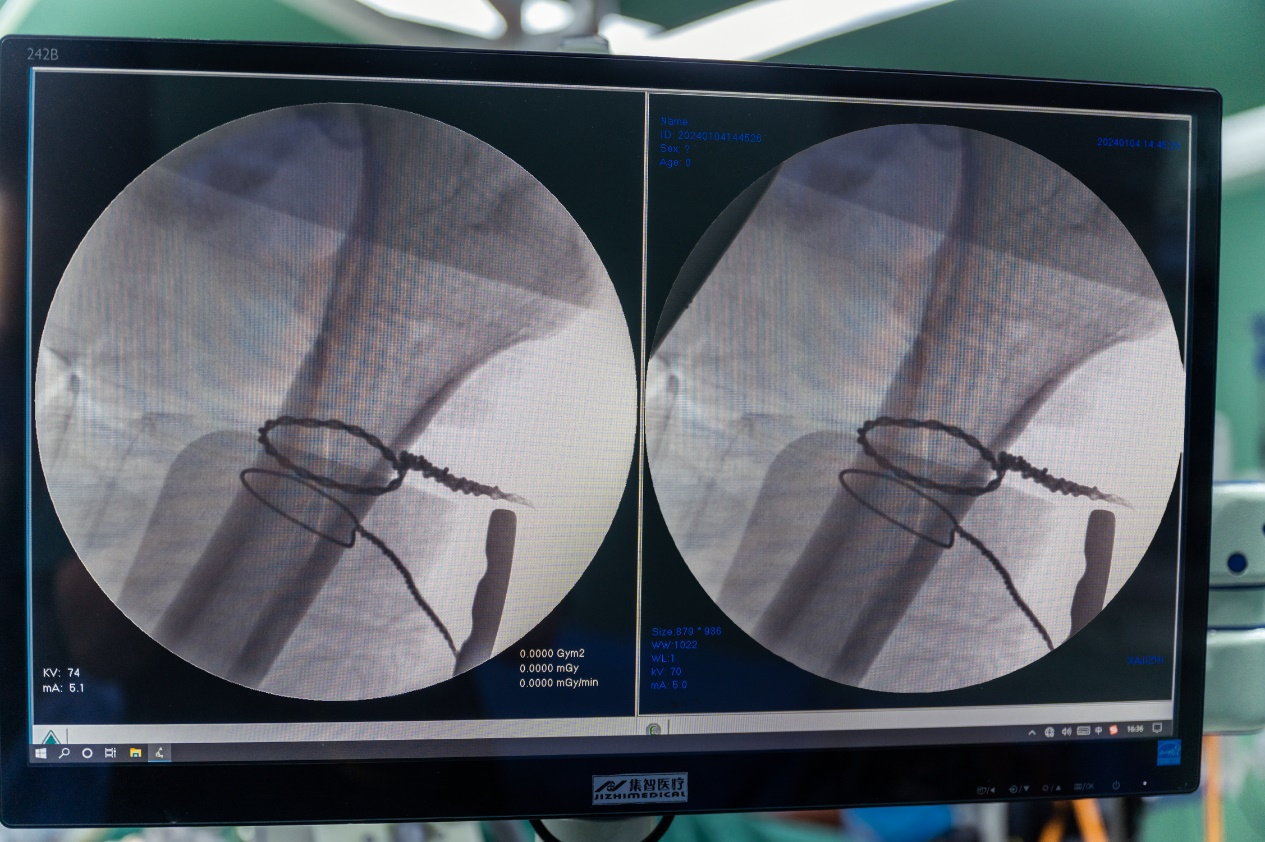

7.牵引下钢丝环扎纠正侧方移位,X线透视解剖复位

8.机器人牵引下进行髓内针固定